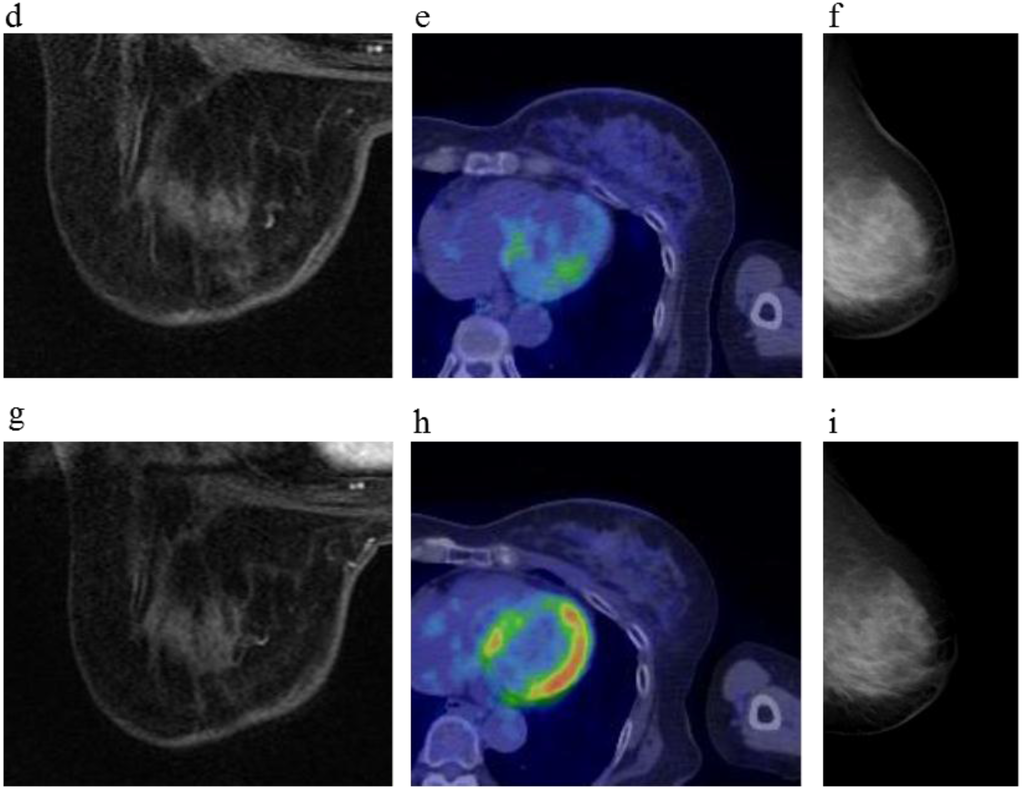

Figure 2.

A 64-year-old female (case 3 in Table 1, Table 2 and Table 3) with left breast cancer (cT2N0M0). CE breast MRI, PET-CT and mammography revealed a breast tumor before KORTUC II therapy, the region of tumor was >20 mm (a–c). After the completion of KORTUC II, the tumor disappeared on the serial examination ((d–f): initial examination after KORTUC II treatment, (g–i): final examination), and no recurrence was identified. The findings of CE breast MRI seems to be most reliable among these three diagnostic modalities in terms of recognition of tumor disappearance.